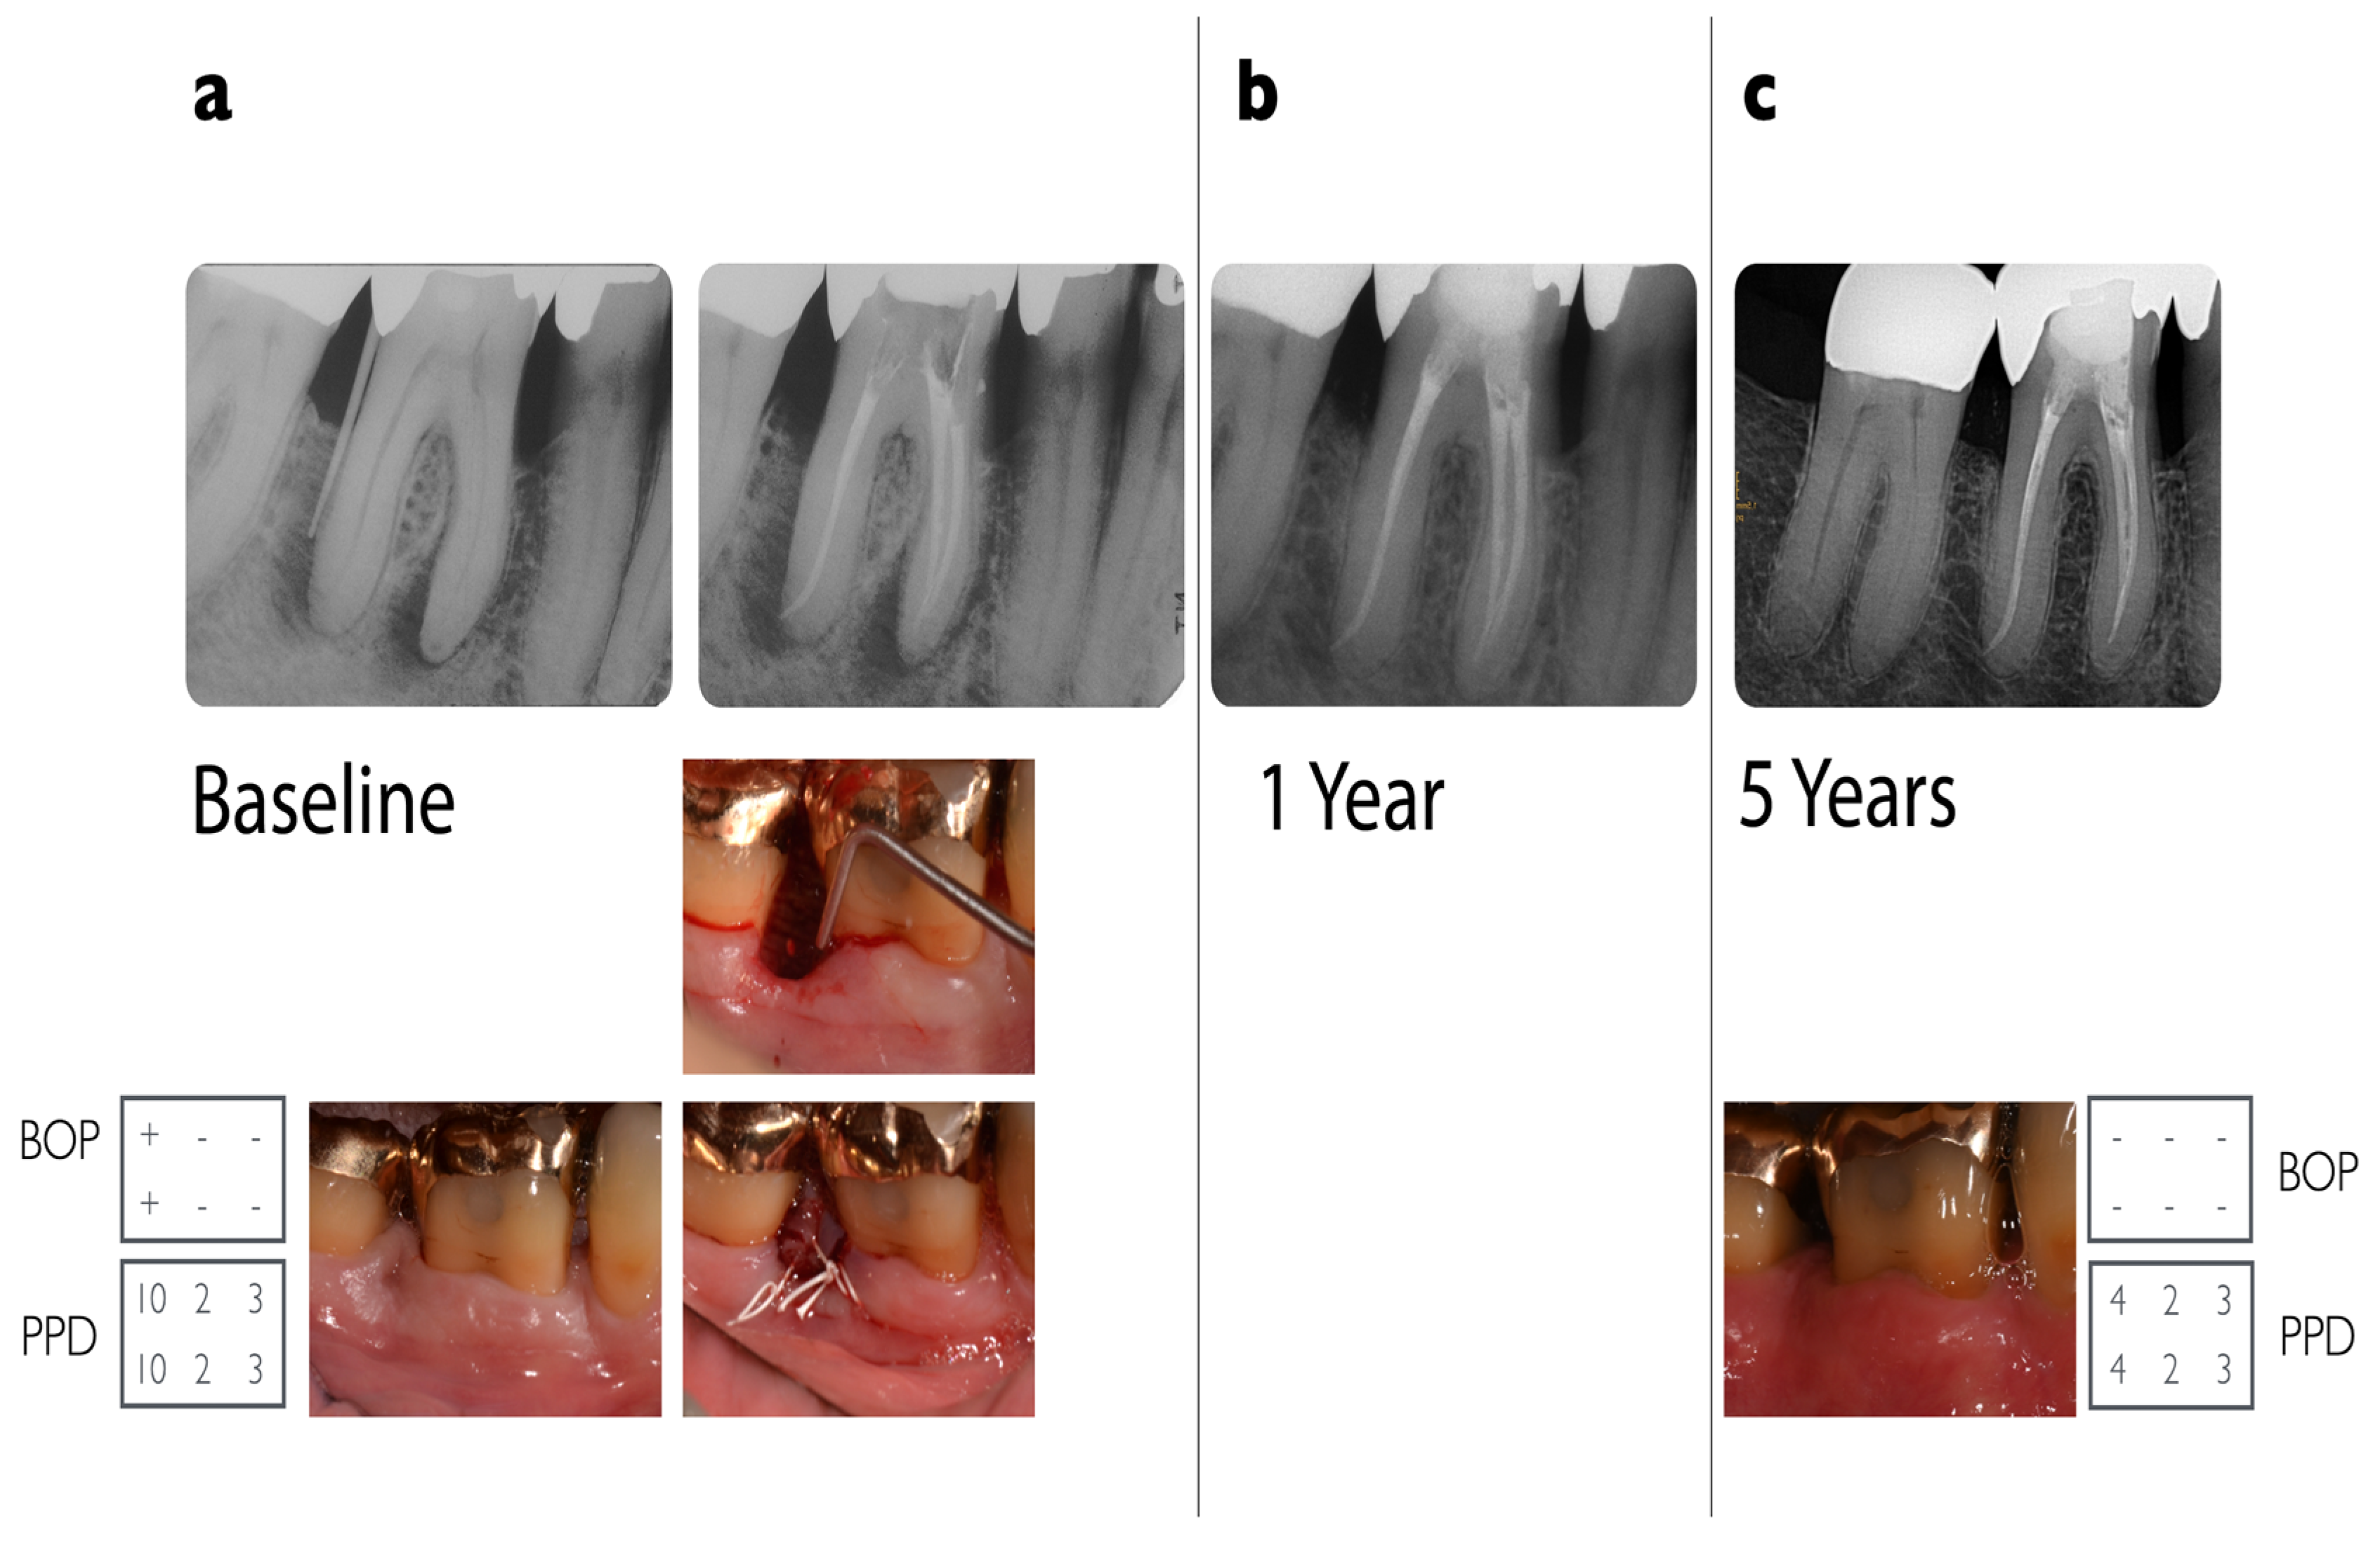

Two representative examples of teeth affected by advanced endo-periodontal lesions that were included in the present analysis are illustrated in Figure 2 and Figure 3.

Figure 2. Radiographic and clinical situation of a lower right molar (#46) in a 55-year-old otherwise healthy patient. Five-year follow-up of a grade 3 endo-periodontal lesion treated with combined endodontic and regenerative periodontal therapy. (a) The patient came for his regular 3-monthly re-evaluation visit for his periodontitis stage III. Deep probing depths at tooth #46 distal of 10 mm (visualized by a gutta-percha point) not evident at his last visit. The furcation was not involved. Radiograph with evidence of extensive vertical and peri-apical bone loss. Pulp sensitivity testing was negative when exposed to chlorethylene and to electric (Vitality Scanner™) scanning. Root canal treatment was performed under an operating microscope. For the regenerative procedure, a papilla preservation flap technique was performed, using DBBM (BioOss-Collagen®Geistlich) and EMD (Emdogain®, Straumann, Basel, Switzerland) as supportive materials. Healing was uneventful, and monofilic sutures (6/0) were used. (b) One-year follow-up with no evidence of radiographic pathologies. (c) Five-year follow-up after regenerative surgery: probing depths: 2–4 mm; recession: up to 3 mm, with a radiograph showing stable radiographic bone fill in the vertical defect area.